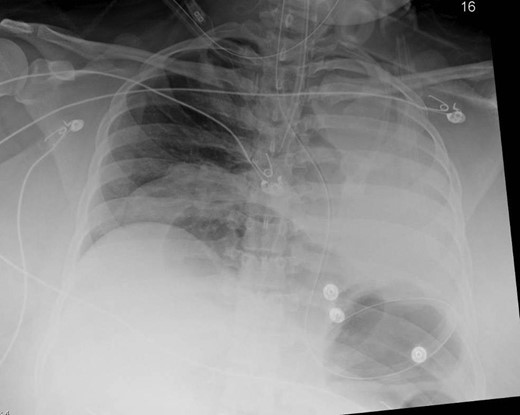

An 18-year-old otherwise healthy female patient presented to a local community hospital emergency department with a 3-day history of non-specific abdominal pain. While at the referring facility, the patients’ pain progressed rapidly to peritonitis. Initial evaluation at the referring facility included a CT scan, which demonstrated herniated large bowel into her thoracic cavity through a suspected anterior/retrosternal hernia (Fig. 1). The patient was transferred to our institution for further management.

Coronal view of herniated colon on computed tomography scan obtained at the referring facility prior to transfer.